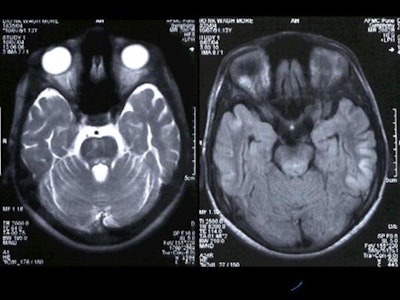

MRI was performed with the following sequences: TSE and gradient-echo T2 and FLAIR axial, TSE T2 sagittal and coronal, 3D Turboflash T1 sagittal with multiplanar reconstructions, and diffusion-weighted images with b-values of 500 and 1000 s/sq mm.

Hyperintensity was also present in the posterior pons and quadrigeminal plate on T2W and FLAIR images, appearing mildly hypointense on T1WI. [Figure 3]